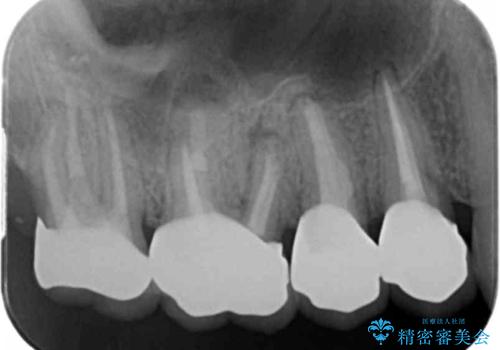

- 近医で「根尖の病変が大きく、残すことができない、歯を抜くしかない。」、と言われ歯を抜く以外の手段がないかを相談しに来院されました。

検査の結果、根管・クリアランス・虫歯といった複合的な問題が認められ、以下のような治療計画を進めることとしました。

根尖病変 →マイクロスコープを用いた精密根管治療の実施

一つ一つの工程を丁寧に行うことで、根尖病変の改善傾向も見られ、安定した歯周環境を整えることができました。